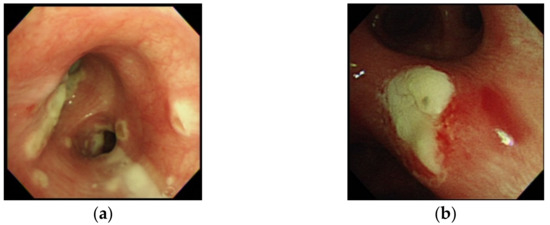

| Tracheobronchitis by bronchoscopy | 6/19 (31.6) | 2/10 (20.0) | 4/9 (44.4) | 0.517 |